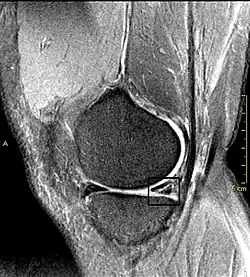

Kreuzbandrisse kommen recht häufig vor. Sie entstehen durch die so genannte Flexions-Valgus-Außenrotations-Stellung. Das heißt, dass das Knie unfreiwillig gebeugt, in die X-Bein-Stellung und nach außen gedreht wird, wobei der Unterschenkel festgestellt ist. Typischerweise entstehen solche Verletzungen beim Skifahren, Handball oder Fußballspielen. Durch das Zerreißen der Bandstrukturen kommt es gleichzeitig zu Gefäßrissen, die eine Blutung in das Kniegelenk (Hämarthros) verursachen. Kreuzbandrisse werden im Schnelltest mittels des vorderen oder hinteren Schubladentests erkannt, d. h. bei gebeugtem Kniegelenk lässt sich das Schienbein gegen den Oberschenkelknochen verschieben und zwar nach vorne (Riss des vorderen Kreuzbands, „vorderes Schubladenphänomen“) oder nach hinten (Riss des hinteren Kreuzbands, „hinteres Schubladenphänomen“). Danach werden die Kreuzbandrisse meist mittels Kernspintomographie diagnostiziert. Behandelt wird ein Kreuzbandriss meistens, indem ein Stück eines anderen Bandes oder einer Muskelsehne entnommen wird, um daraus eine Kreuzbandplastik herzustellen.

Als bildgebende Verfahren werden Röntgenaufnahmen, Sonographie, Arthrographie (kaum mehr angewendet), Magnetresonanztomographie (MRT) und Computertomographie (CT) eingesetzt. Eine Arthroskopie kann zur Darstellung innerer Strukturen angewendet werden.